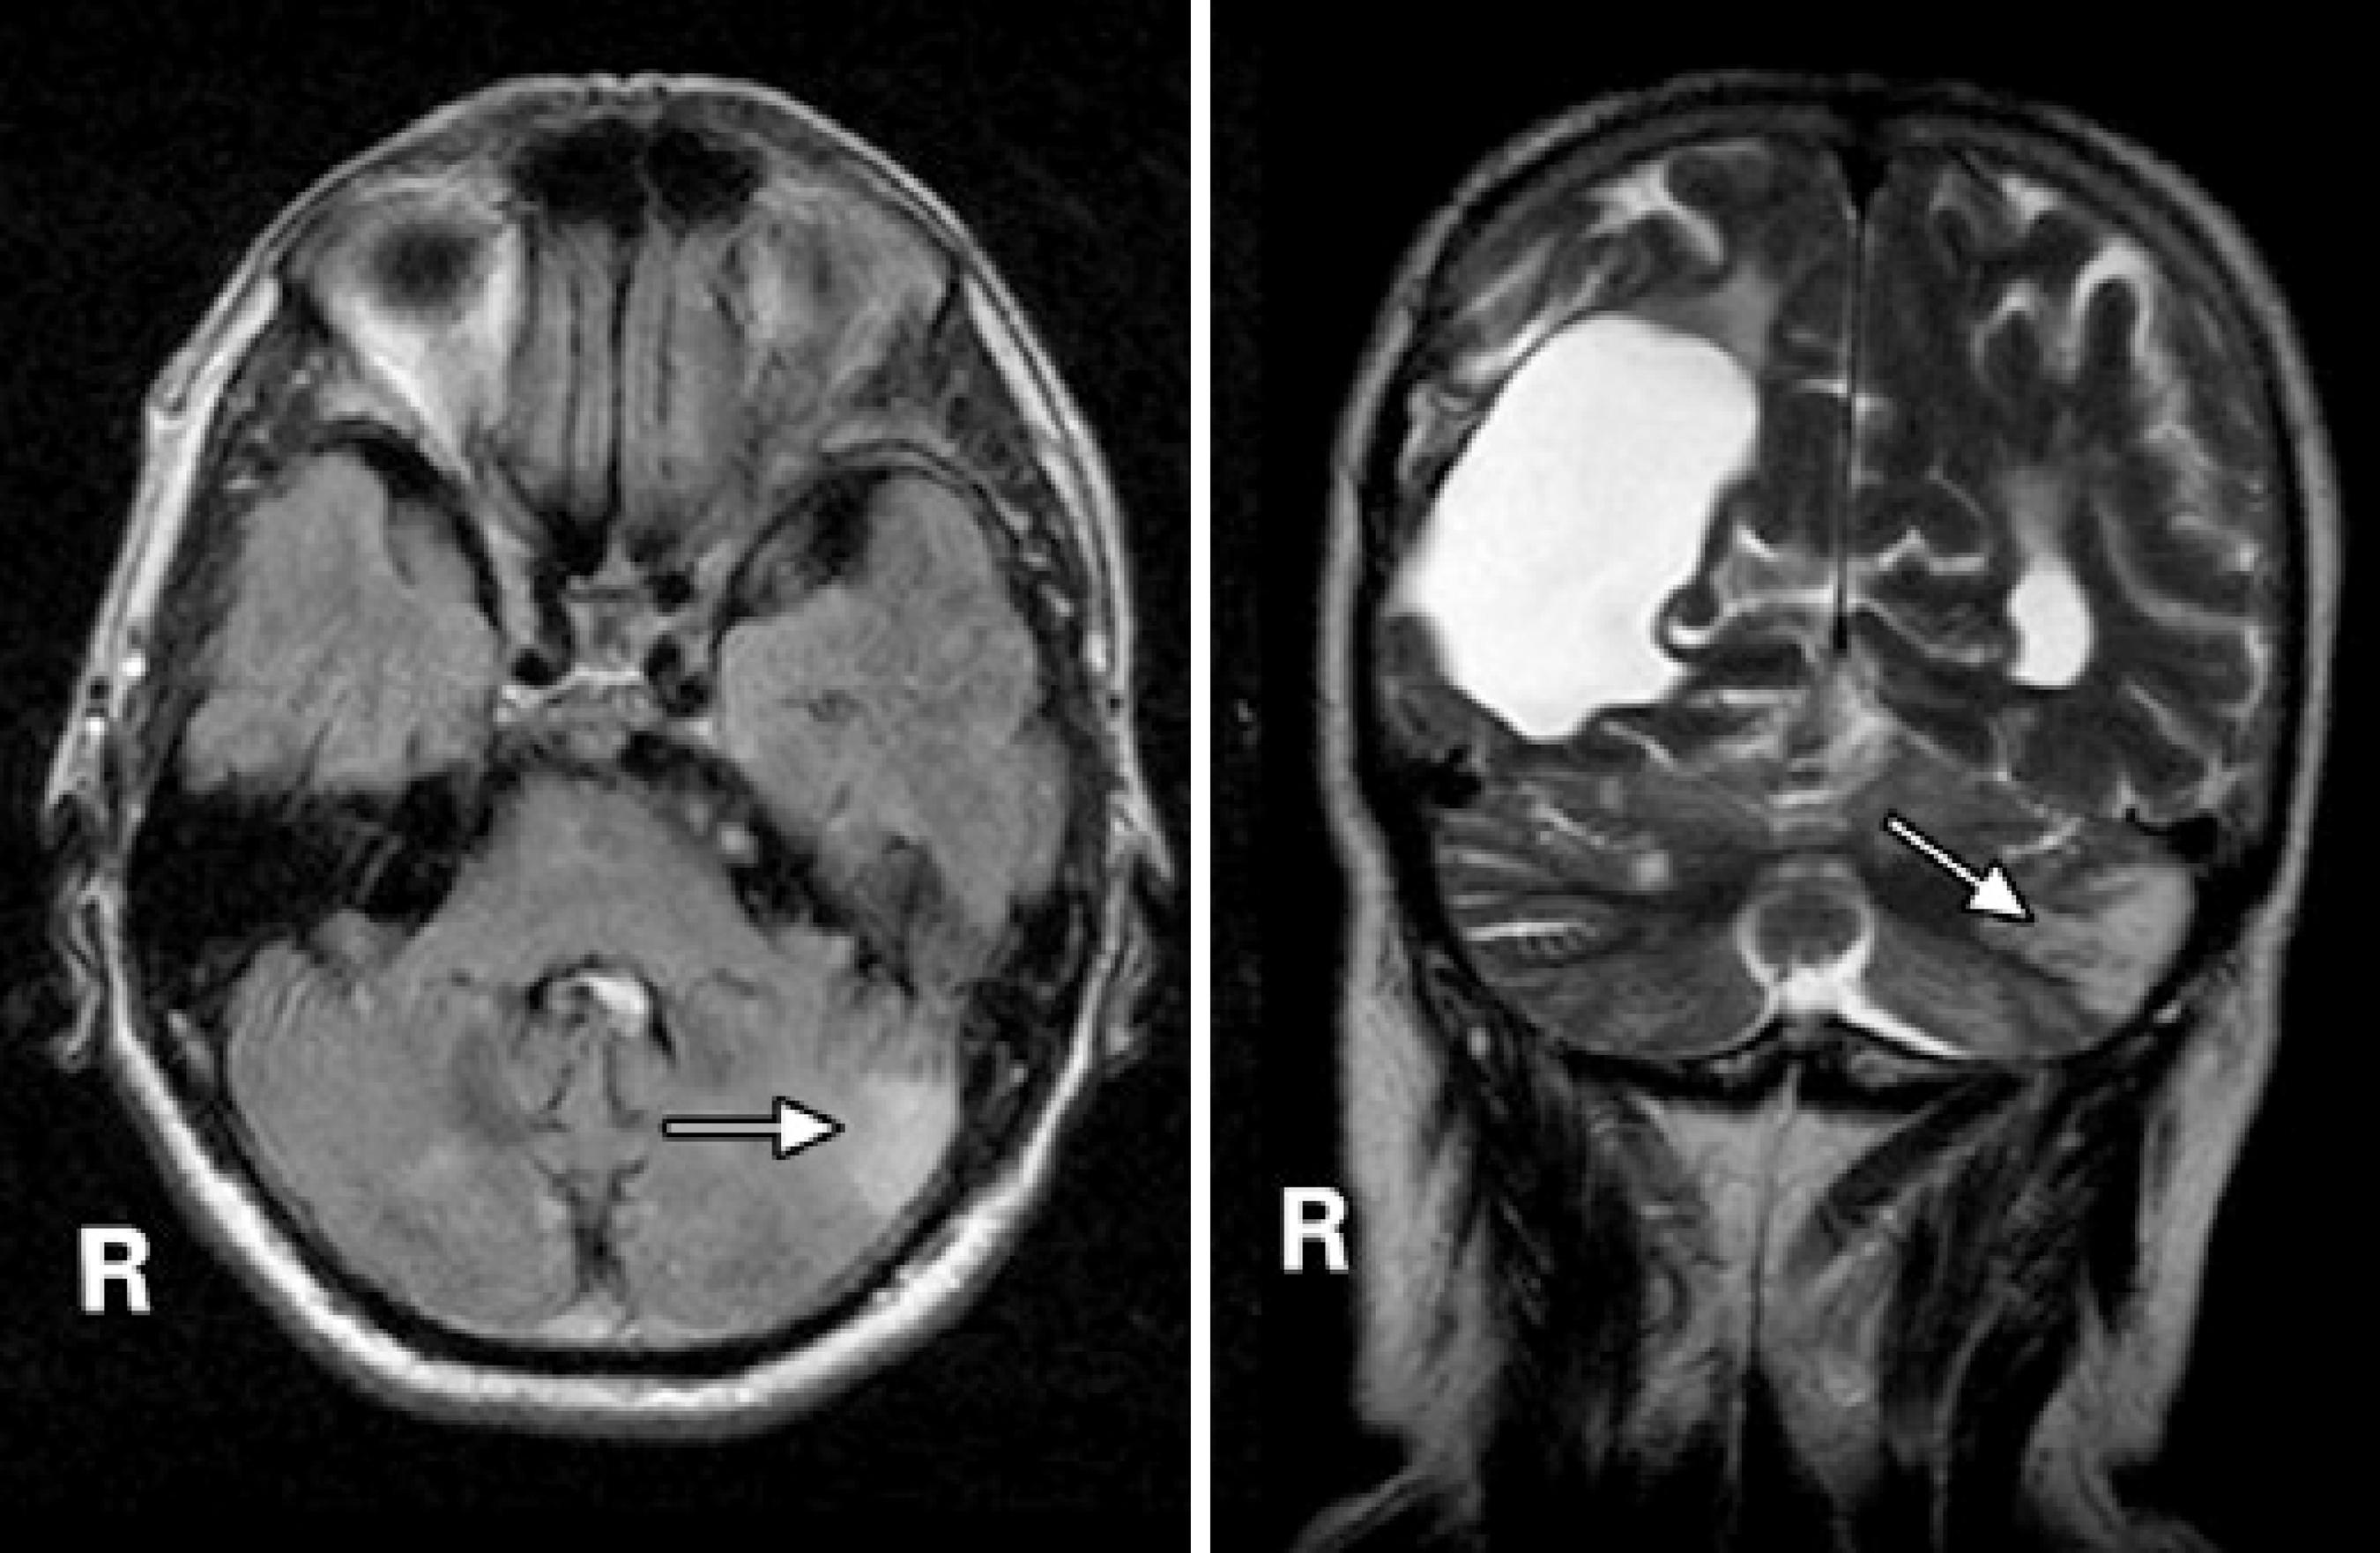

On admission, physical examination revealed a blood pressure of 200/176 mmHg. His visual acuity was classified as “counting fingers” in both eyes, but one hour later it deteriorated to “no light perception” in both eyes. The eye fundus examination was normal (Figure 1). The patient’s pupils were isochoric with a normal light reflex. Neurologic examination showed mental confusion and the electroencephalography revealed slow background activity and the loss of alpha rhythm in the posterior pole. Blood laboratory tests revealed no abnormalities. Electrocardiography and the chest X-ray were normal. An immediate computed tomography (CT) scan was negative for intracranial hemorrhage but showed dilation of the right occipital horn and moderate signs of cortical and subcortical atrophy. Magnetic resonance imaging (MRI) acquired 24 hours after admission revealed a cortical hyperintense lesion in the left cerebellar hemisphere and an enlarged right ventricle judged to be secondary to a previous infarct (Figure 2). In addition, apparent diffusion coefficient maps obtained during the PRES revealed increased diffusion in the occipital regions indicative of vasogenic edema (Figure 3).

Figure 2 Axial FLAIR-weighted (left) and coronal T2-weighted (right) images showing a hyperintense lesion in the left cerebellar hemisphere (arrows). Note the enlarged right ventricle secondary to a previous infarct.

Typical imaging features of PRES include hypodense regions within the posterior white matter regions on unenhanced CT scans and areas of hyperintense signal on T2-weighted MRI images. Diffusion-weighted MRI and quantification of the apparent diffusion coefficient usually reveal vasogenic edema in the parieto-occipital regions of both cerebral hemispheres. The subcortical white matter is always affected and the cortex is often involved. The edema is usually asymmetric, but almost always bilateral(4). Lesions are not enhanced after the administration of contrast material. In our case, MRI revealed a hyperintense lesion in the left cerebellar hemisphere with vasogenic edema in the occipital regions.